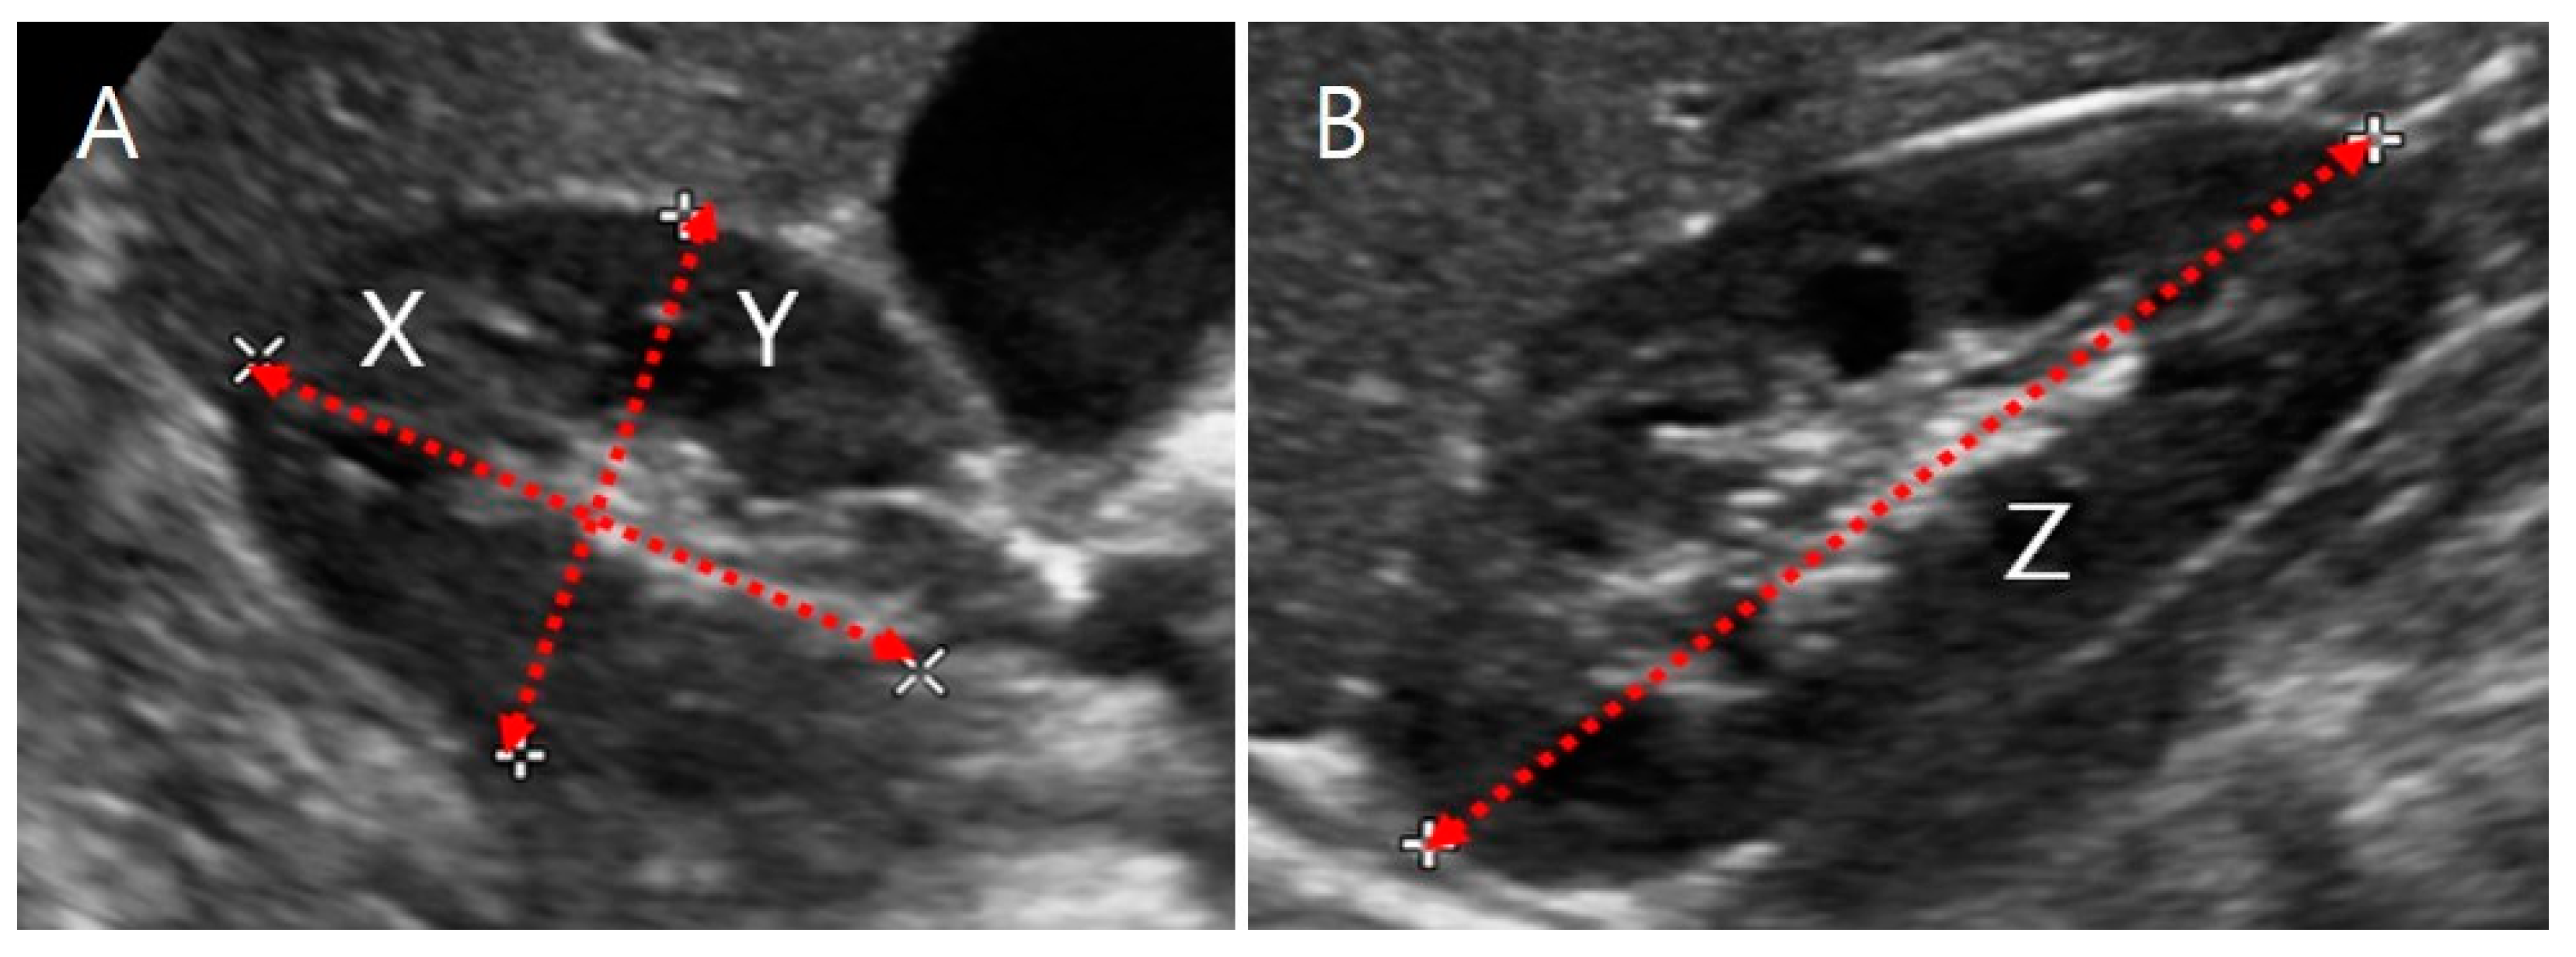

where the length of the kidney (Z, maximum bipolar length) was measured in the coronal plane, while the depth (X, maximum length parallel to the hilum) and the width (Y, maximum length perpendicular to X) were measured in the transverse hilar region (Figure 1).

ELLIP_Vol = depth (X) (cm) × width (Y) (cm) × length (Z) (cm) × π/6,

Ultrasound image of a kidney. (A) Transverse section. X is the maximum depth of the kidney parallel to the hilum, and Y is the maximum width perpendicular to X. (B) Coronal section. Z is the maximum bipolar length.